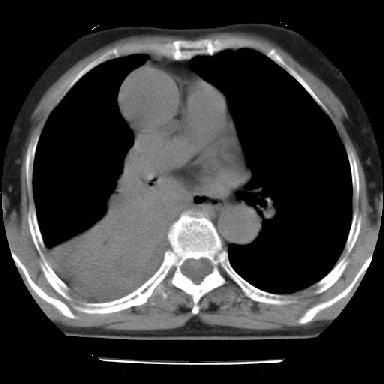

以下是引用苯小孩在2007-4-13 16:20:00的发言:[br]1、右下肺中央型肺癌并阻塞性肺不张、肺内转移、胸椎右侧附件亦有转移<横断层面第8层>.[br]2、右侧胸腔积液.

以下是引用swyyy2007在2007-4-13 15:31:00的发言:[br]右肺门下区肿块,右肺下叶支气管阻塞,右肺下叶不张,右侧大量胸腔积液,右肺中叶见结节状高密度影,边缘清,纵隔内见肿大淋巴结。首先考虑右下肺中心型肺癌伴右肺下叶不张、中叶、纵隔淋巴结转移。右侧胸腔积液。